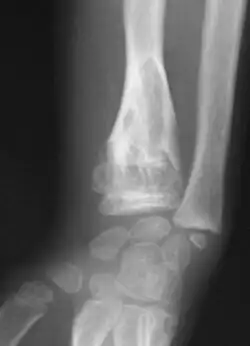

X-ray image showing enchondromas localized in the lower part of the radius of a 7-year-old girl with Ollier disease.

Abnormal bone growth such as shortening or thickening and deformity may be observed in patients of Ollier disease. These bone lesions are visible at birth using radiography but are usually not screened or examined for until clinical manifestations present during early childhood. However, some patients may exhibit no signs of any symptoms.[1] One study found thirteen to be the mean age of diagnosis in patients with Ollier disease. In an X-ray, there would normally be the presence of several homogeneous lesions of an oval or elongated shape with bone edges that are slightly thickened.[3] With age, these lesions may calcify and appear as diffusely minute spots or stippled. Fan-like septations or streaks would be indicative of the presence of several enchondromas. Early detection and consistent and repeated monitoring is important in order to prevent and treat any potential bone neoplasms.